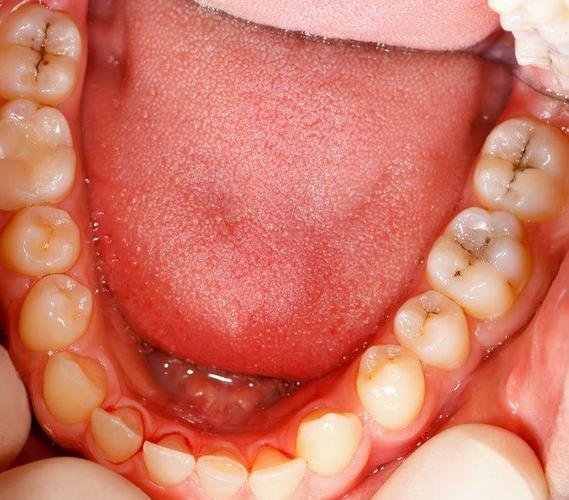

由于人类下颌骨的退化,下颌智齿出现萌出不全的情况,而牙冠表面覆盖着众多龈瓣,因此如果不小心受到感染了,牙冠周围的软组织就会出现炎症,也就是智齿冠周炎。

急性局限型冠周炎:一般情况下,这类炎症会导致阻生牙牙冠上的龈瓣发红肿胀,同时并有压痛感。对其进行挤压时,会有食物残渣或者一些脓性物溢出来。反复出现急性局限性冠周炎的患者,可出现龈瓣增生的情况。

导致张口困难,影响进食:由于阻生牙的萌出不全,后侧牙龈覆盖在阻生牙上方,导致部分牙冠会形成冠周袋,食物和细菌会经常留存在冠周袋中,导致局部软组织感染发炎,进而影响人们张口进食。